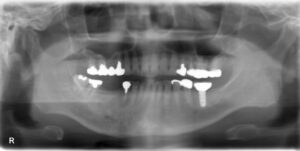

下顎大臼歯4本欠損症例

BEFORE AFTER 56歳女性/下顎4本欠損/インプラント埋込手術 【治療内容】 右下大臼歯2本は歯根の破折のため…